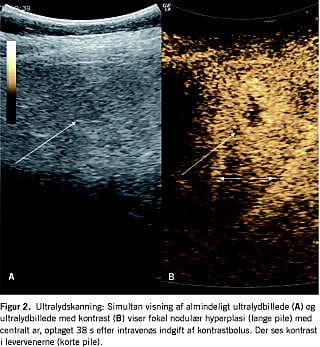

Ultralydundersøgelse af abdomen blev gennemført hos 23 patienter (Figur 2 ). I elleve tilfælde fandt man en hypo- til isoekkoisk proces. I fem skanninger var processen hyperekkoisk, og i fire skanningsbeskrivelse blev ekkoforholdene ikke angivet. I tre tilfælde var det ikke lykkedes at synliggøre FNH-læsionen ved ultralydundersøgelse, men ved supplerende billeddiagnostik. I ingen af tilfældene blev diagnosen FNH stillet.

Fokale processer i leveren kan karakteriseres dynamisk med CT, MR- eller ultralydskanninger efter intravenøs administration af en bolus af et relevant kontrastmiddel. Dermed opnås højere specificitet og sensitivitet [17]. Kontrastopladningen i FNH kan vise den typiske arterielle forsyning og det centrale ar. Påvises FNH ved to uafhængige billeddiagnostiske undersøgelser, vil biopsi kunne udelades. Biopsi anbefales dog fortsat ved atypisk billeddiagnostik eller ved klinisk mistanke om malignitet. I dette studie var kun to MR-undersøgelser diagnostiske af alle de billeddiagnostiske undersøgelser, og i begge tilfælde valgte man alligevel at bioptere.